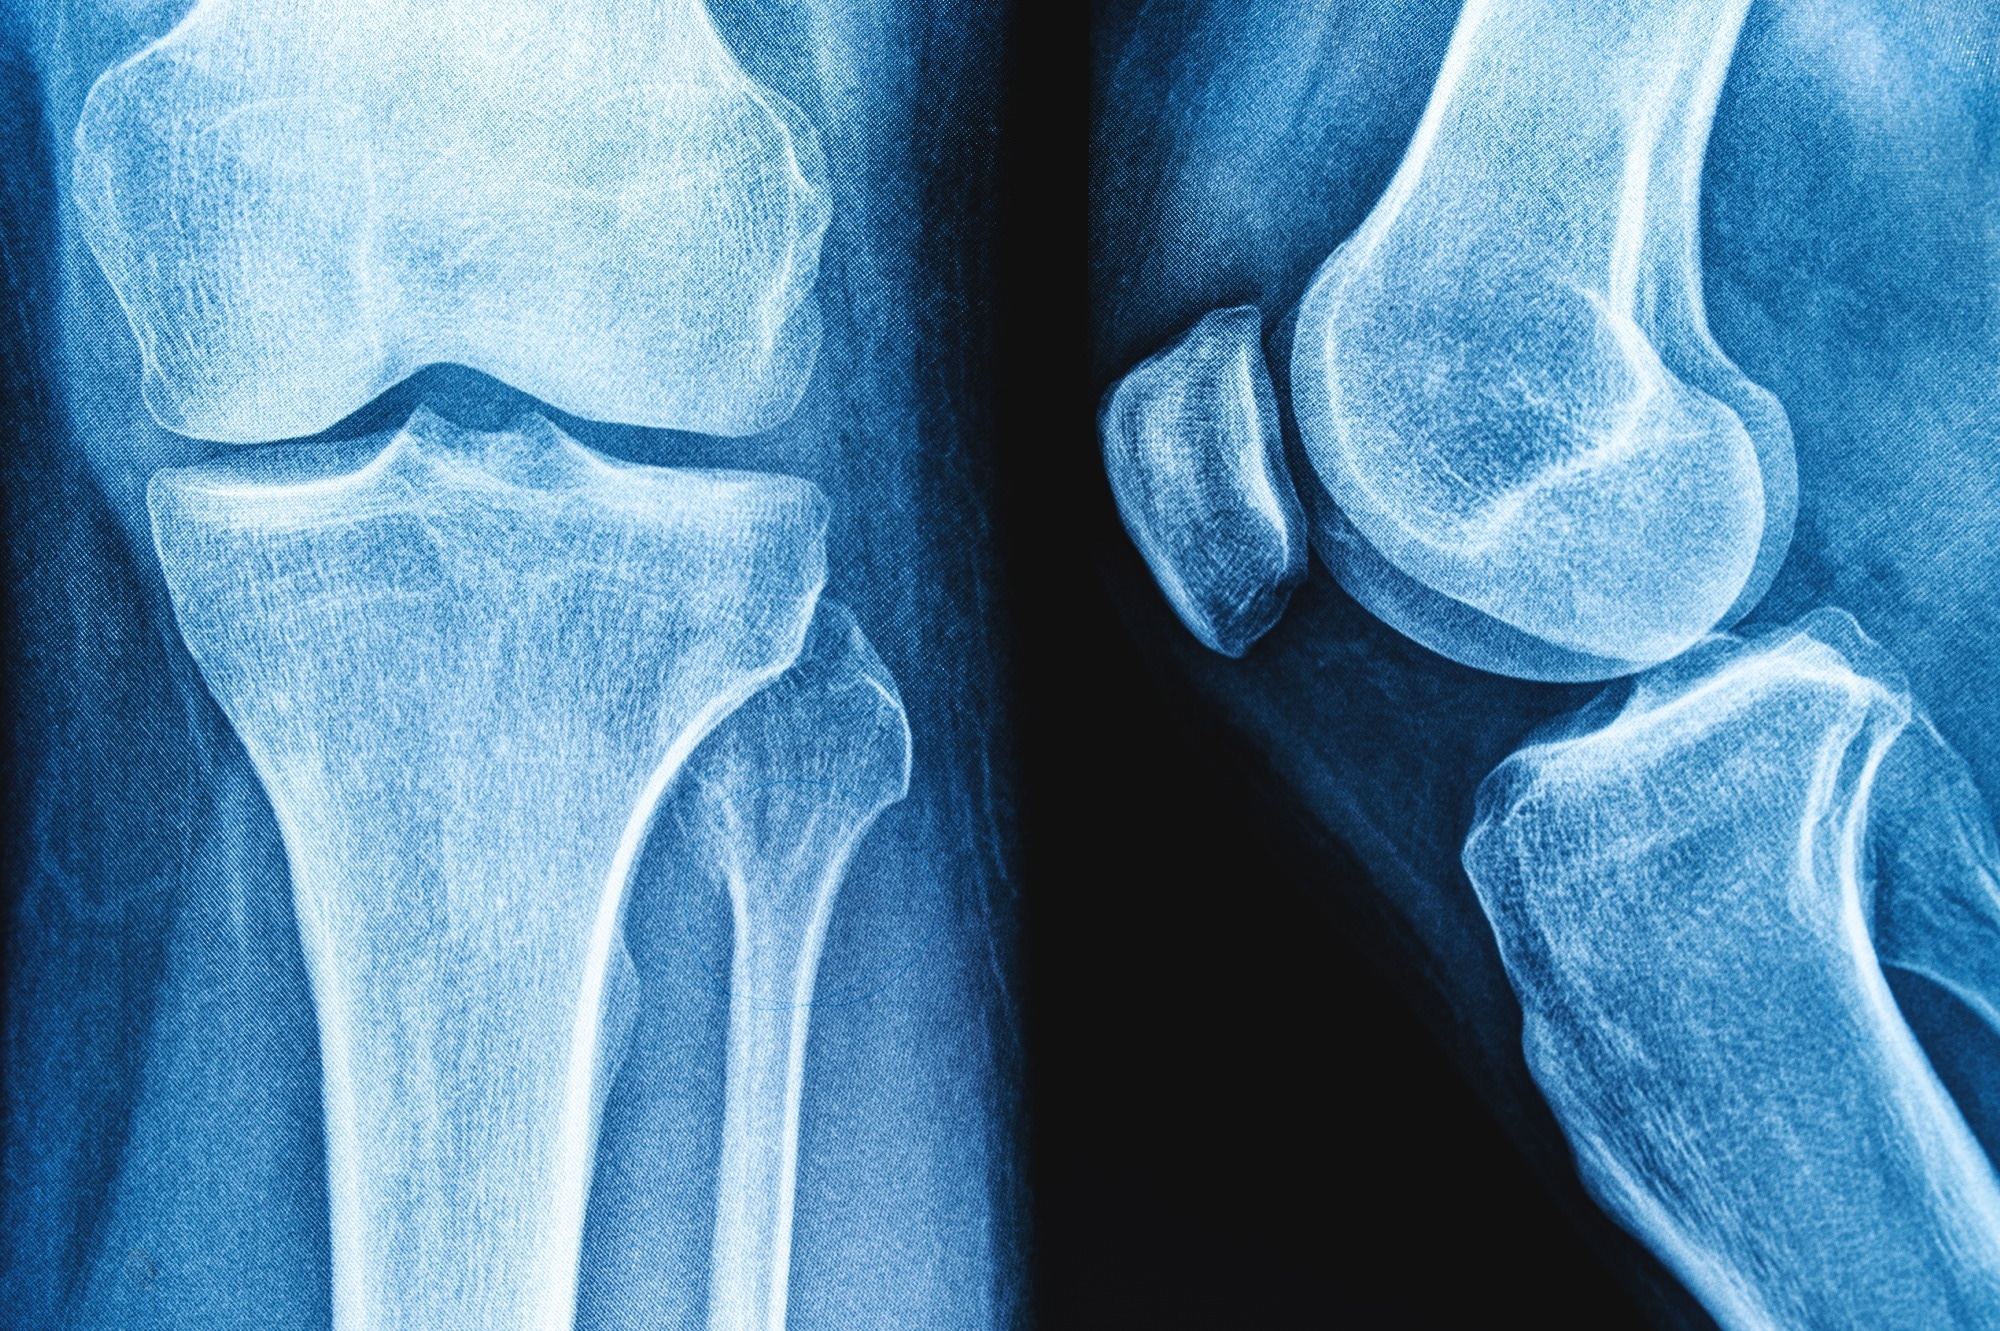

Review: Impact of yogurt consumption on bone health markers in adults with or without osteoporosis: a systematic review and meta-analysis. Image Credit: siamionau pavel / Shutterstock